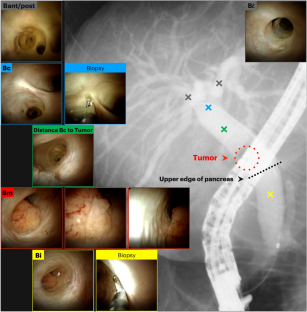

Recently, the number of reports describing patients with initially unresectable biliary tract cancer (BTC) who underwent resection in the form of conversion surgery is increasing. Gemcitabine plus cisplatin (GC) combination therapy has been reported to significantly prolong the median survival time from 8.1 to 11.7 months compared with conventional gemcitabine therapy in patients with unresectable BTC. We report the case of a patient with unresectable BTC who underwent conversion surgery with a partial response to GC combination therapy. A 78-year-old woman was diagnosed with unresectable BTC with invasion of the right hepatic artery by lymph node metastasis and liver metastases. The patient received GC combination therapy. After 6 cycles of chemotherapy, the patient achieved a partial response. The radiological findings revealed a marked shrinkage in the primary lesion and the disappearance of lymph node and liver metastases. Therefore, the patient underwent conversion surgery, including biliary tract resection and regional lymph node dissection. For postoperative follow-up, the patient was monitored without receiving adjuvant chemotherapy. The patient had not exhibited recurrence during the 12-month follow-up period. We report the case of a patient with unresectable BTC who underwent conversion surgery with a partial response to GC combination therapy.